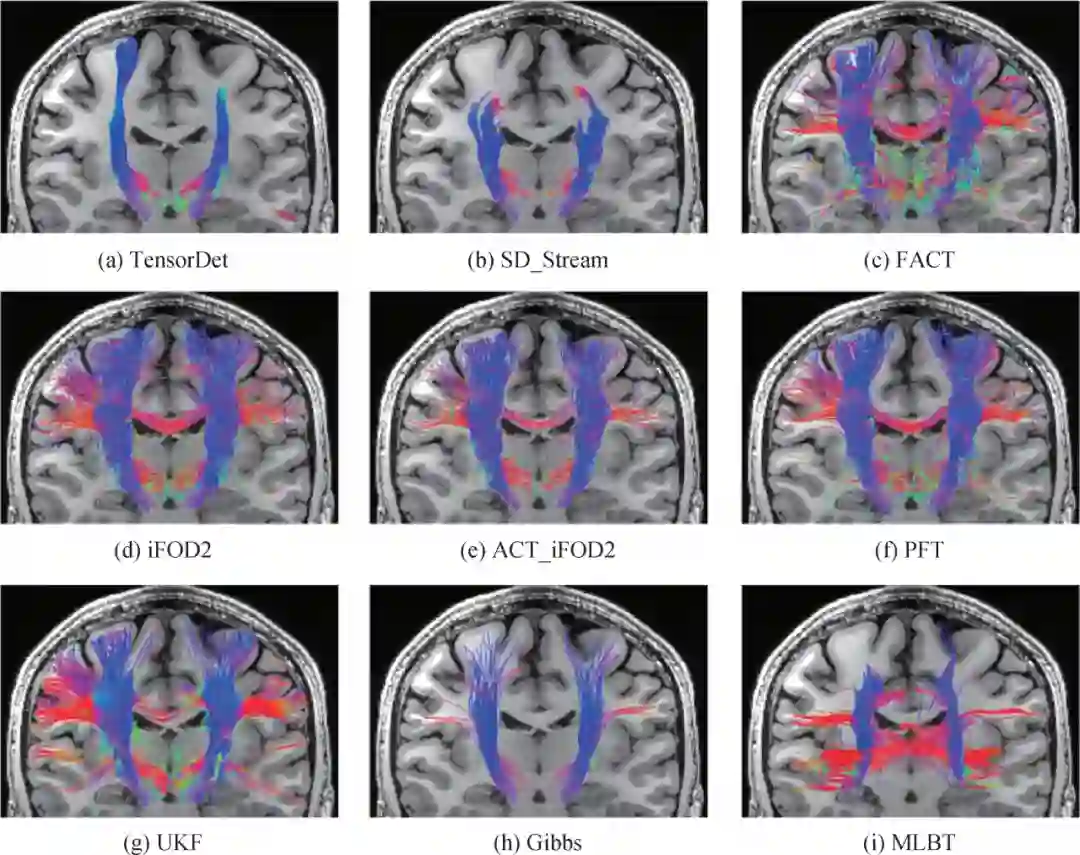

论文对9种常用跟踪算法进行实验对比:基于张量的流线型跟踪(TensorDet)、基于球面反卷积的流线型跟踪(SD_Stream)、纤维联络连续跟踪(FACT)、纤维方向分布跟踪(iFOD2)、解剖学约束纤维方向分布跟踪(ACT_iFOD2)、粒子滤波跟踪(PFT)、无迹卡尔曼滤波跟踪(UKF)、吉布斯跟踪(Gibbs)和机器学习跟踪算法(MLBT),其中TensorDet、SD_Stream、FACT为确定型算法,iFOD2、PFT、UKF、ACT_iFOD2为概率型算法,Gibbs为全局型算法,MLBT为机器学习算法。

图5  临床数据不同跟踪算法皮质脊髓束区域跟踪结果

图6 临床数据不同跟踪算法胼胝体区域跟踪结果